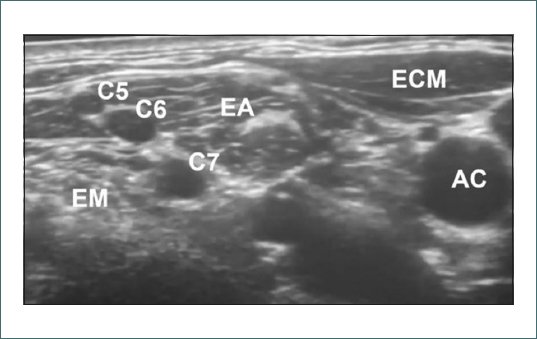

Se coloca a la paciente en decúbito supino con la cabeza girada hacia el lado opuesto al que se bloquea y se realiza asepsia de la zona. A continuación, se moviliza lentamente el transductor en dirección cefálica mientras se visualiza de forma continua el plexo braquial hasta identificarlo entre los músculos escalenos anterior y medio (Fig. 1). Debido a la presencia de una masa adenopática estos se encuentran desplazados cranealmente y presentan una leve distorsión anatómica. Mediante un abordaje en plano y con el uso de neuroestimulación, se introduce la aguja de lateral a medial, localizando el plexo a 2 cm de profundidad y se procede a la colocación del catéter. Tras una aspiración cuidadosa se administran 8 ml de lidocaína 2%, con reducción significativa del dolor (EVA 5-6/10). Posteriormente, se mantiene una infusión continua a 2 ml/h de ropivacaína 2% + fentanilo (2 mcg/ml).

Figura 1. Ultrasonido del plexo braquial a nivel interescalénico. C5, C6, C7: nervios espinales cervicales del quinto al séptimo; EM: escaleno medio; EA: escaleno anterior; ECM: esternocleidomastoideo; AC: arteria carótida.